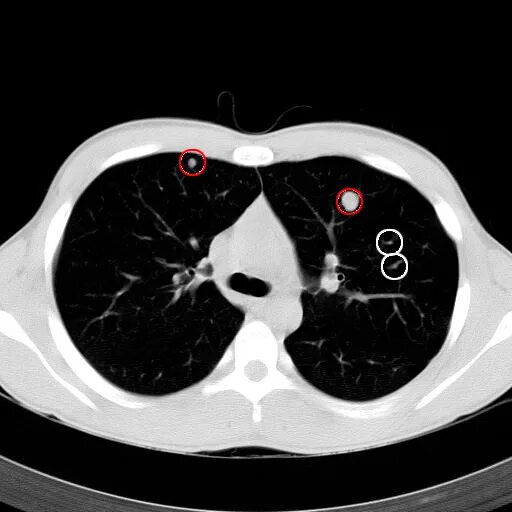

Ct search